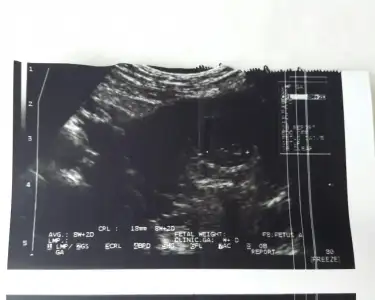

Merhaba 7+4 karından bakıldı cinsiyet yorumlar mısınız ?

Eklentiler

• 45F5D451-8E5E-478A-BBC1-0AB0FA1AEE6F.webp

45F5D451-8E5E-478A-BBC1-0AB0FA1AEE6F.webp

17,2 KB · Görüntüleme: 132